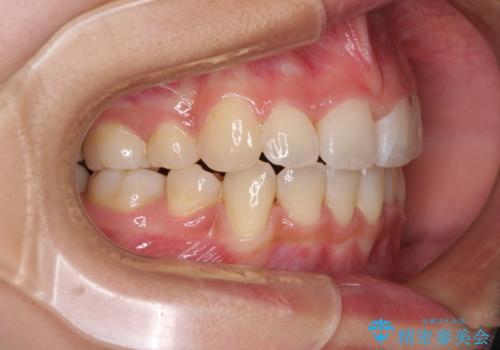

- 上下前歯のデコボコと、それによる磨きづらさを気にして来院された患者様です。

叢生解消のため、上下左右第一小臼歯4本を抜歯し、ワイヤー装置にて矯正治療を行うこととしました。

半年ほどで前歯のデコボコは改善され、汚れの溜まりやすさは解消されました。

抜歯スペースを閉じるために期間がかかりましたが、当初予定通り2年強で終えることができました。